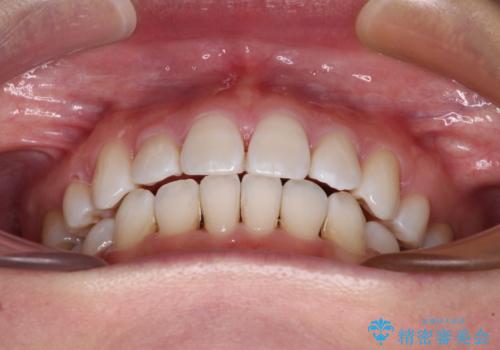

出っ歯を改善 目立たないワイヤー装置での抜歯矯正

- 口元の突出感と口の閉じにくさを気にして来院された患者様です。

上下左右第一小臼歯4本を抜歯し、ワイヤー装置にて口元を引っ込めるよう矯正治療を行うこととしました。

2年~2年半が治療期間の目安でしたが、順調に治療が進み、1年9か月で満足のいく歯列となりました。